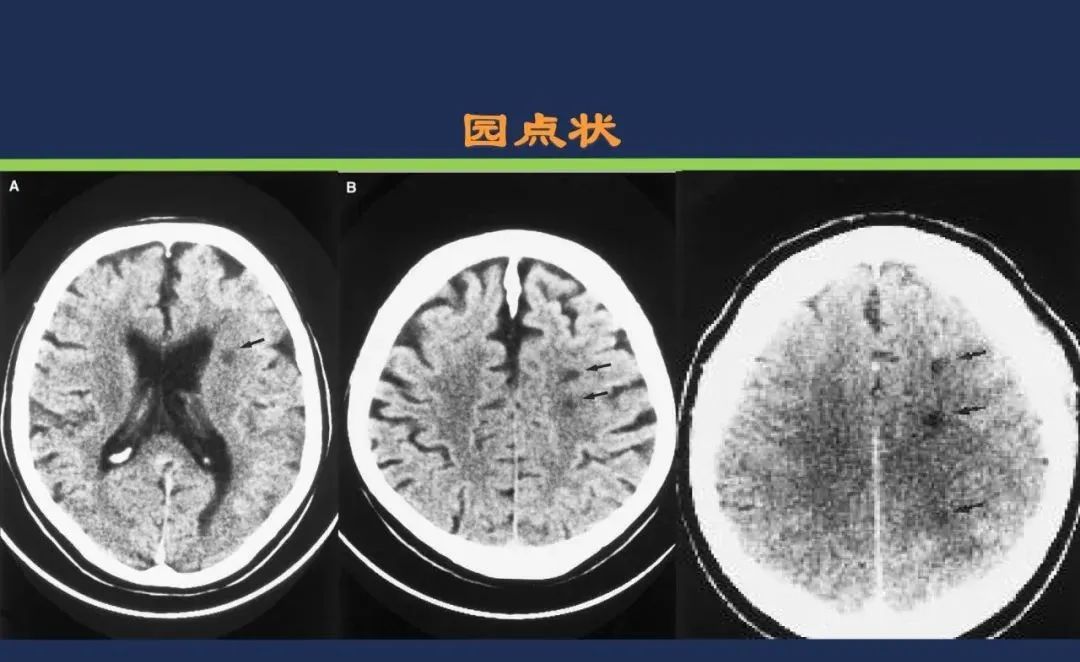

从梗死部位推测责任血管

颈内动脉系统梗死颈内动脉大脑中动脉

分水岭梗死皮质前型+皮质后型+后上型皮质下前型+皮质下后型+皮质下上型+皮质下外型+皮质下下型